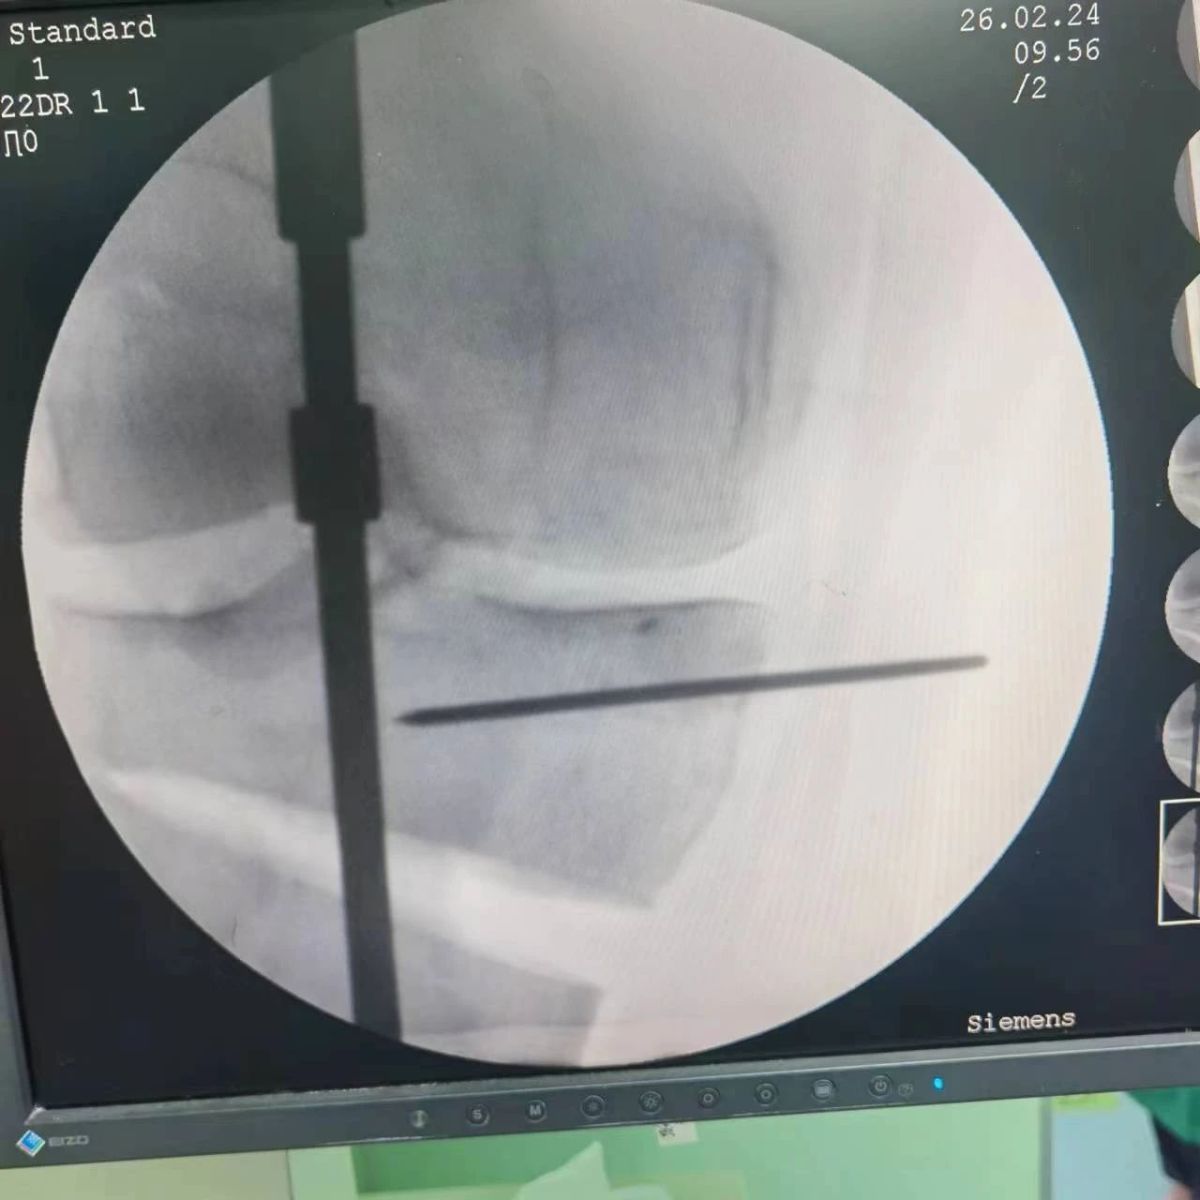

2月26日,漯河市骨科醫(yī)院(漯河醫(yī)專二附院、漯河市立醫(yī)院)膝關(guān)節(jié)外科、運(yùn)動(dòng)損傷科(骨六科)在保膝治療方面取得了新的突破,李付彬主任帶領(lǐng)岳龍等團(tuán)隊(duì)醫(yī)師,順利完成“計(jì)算機(jī)精準(zhǔn)術(shù)前規(guī)劃聯(lián)合3D打印截骨導(dǎo)板輔助脛骨高位截骨治療膝關(guān)節(jié)骨性關(guān)節(jié)炎”的手術(shù),這在漯河市尚屬首例!

患者為一名45歲男性,查體及X片可見(jiàn)明顯的膝內(nèi)翻,內(nèi)翻畸形主要來(lái)源于脛骨近端,關(guān)節(jié)鏡下可見(jiàn)內(nèi)側(cè)間室軟骨全層磨損,疼痛較重,年紀(jì)輕輕幾乎喪失工作能力。對(duì)于這種日?;顒?dòng)需求比較大的患者朋友,我們盡最大可能給予保膝治療,李付彬主任給患者詳細(xì)講解了保膝治療的方案(脛骨近端高位截骨)及預(yù)期效果,給患者帶來(lái)了極大希望。為了更精確、更微創(chuàng)的治療,李付彬主任團(tuán)隊(duì)緊跟國(guó)內(nèi)外科技前沿,采用計(jì)算機(jī)精準(zhǔn)術(shù)前規(guī)劃,并設(shè)計(jì)3D打印截骨導(dǎo)板,力求給患者帶來(lái)更精準(zhǔn)、更安全的手術(shù)效果。

李付彬主任團(tuán)隊(duì)通過(guò)精準(zhǔn)術(shù)前規(guī)劃,設(shè)計(jì)目標(biāo)力線及調(diào)整撐開(kāi)角度,轉(zhuǎn)化成需要撐開(kāi)的高度,最終設(shè)計(jì)出同等高度的填充塊,術(shù)中驗(yàn)證力線調(diào)整與術(shù)前規(guī)劃完全一致!

鋼板位置、螺釘位置及長(zhǎng)度均可通過(guò)術(shù)前規(guī)劃計(jì)算,術(shù)中通過(guò)定位操作,基本與術(shù)前規(guī)劃一致,手術(shù)快速高效完成,外側(cè)合頁(yè)保留完整。無(wú)任何并發(fā)癥出現(xiàn)。術(shù)后見(jiàn)鋼板位置及力線糾正近乎完美!